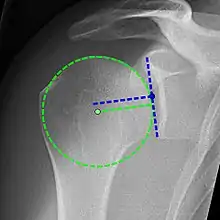

Xray

X-ray projectional radiography cannot directly reveal tears of the rotator cuff, a 'soft tissue', and consequently, normal X-rays cannot exclude a damaged cuff. However, indirect evidence of pathology may be seen in instances where one or more of the tendons has undergone degenerative calcification (calcific tendinitis). The humeral head may migrate upward (high-riding humeral head) secondary to tears of the infraspinatus, or combined tears of the supraspinatus and infraspinatus.[51] The migration can be measured by the distance between:

- A line crossing the center of a line between the superior and inferior rims of the glenoid articular surface (blue in image).

- The center of a "best-fit" circle positioned over the humeral articular surface (green in image)

Normally, the former is positioned inferiorly to the latter, and a reversal therefore indicates a rotator cuff tear.[51] Prolonged contact between a high-riding humeral head and the acromion above it may lead to X-ray findings of wear on the humeral head and acromion; secondary degenerative arthritis of the glenohumeral joint (the ball and socket joint of the shoulder), called cuff arthropathy, may follow.[50] Incidental X-ray findings of bone spurs at the adjacent acromioclavicular joint may show a bone spur growing from the outer edge of the clavicle downward toward the rotator cuff. Spurs may also be seen on the underside of the acromion, once thought to cause direct fraying of the rotator cuff from contact friction, a concept currently regarded as controversial.